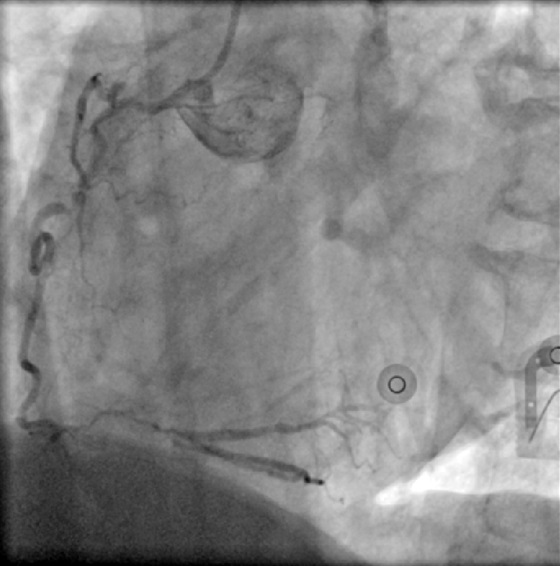

Suboptimal balloon dilation led to implantation of a 2.75 ¡¿ 8 mm Onyx DES at the LCX ostium. The LAD was predilated and treated with 2.0 ¡¿ 38 mm and 2.5 ¡¿ 38 mm Xience Sierra stents plus a 3.5 ¡¿ 15 mm Megatron for LM–LAD. IVUS confirmed full stent expansion and apposition with no residual stenosis. A minor LAD ostial type II dissection was observed but without flow limitation.

Final angiography showed excellent patency. ECMO was removed uneventfully, and manual hemostasis achieved due to femoral aneurysms precluding device closure.